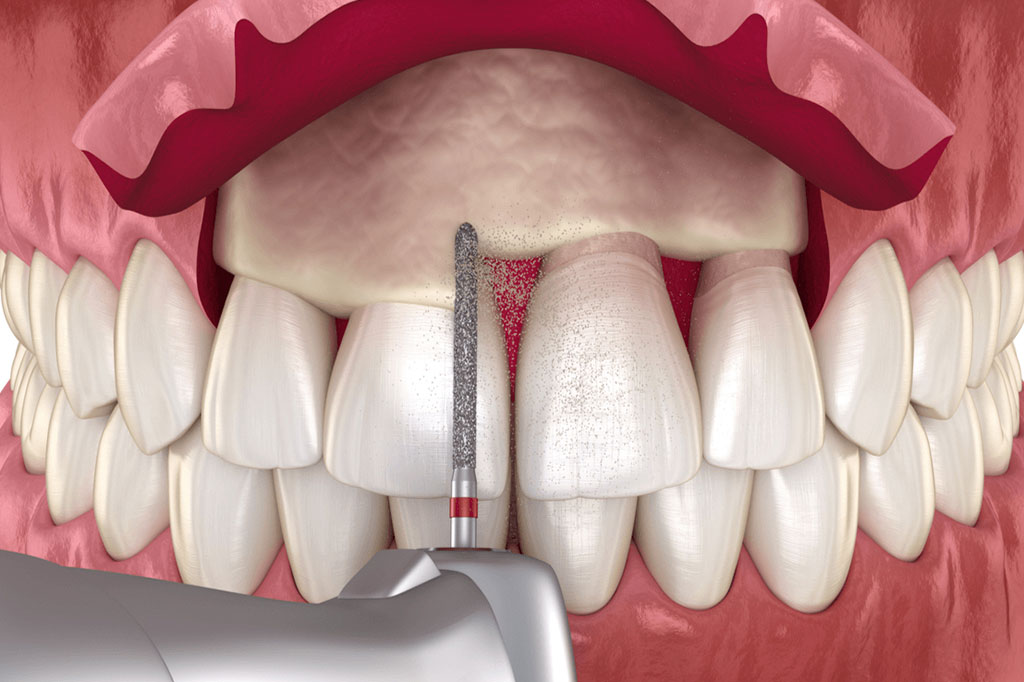

A gingivektómia egy sebészeti eljárás, amely során az ínyszövet egy részét eltávolítjuk. Ezt a beavatkozást általában a fogínybetegségek kezelésére, a mély ínytasakok megszüntetésére, vagy az esztétikai megjelenés javítására végezzük.